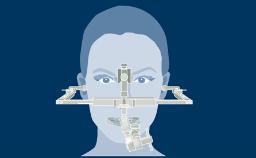

Todos os profissionais de saúde que fazem cirurgia de implante encontrarão complicações durante toda a vida profissional. Tais complicações podem ocorrer por várias razões diferentes, mas a maioria pode ser explicada como percalços ou erros cirúrgicos e/ou protéticos. Este módulo de aprendizado fornecerá uma visão geral das complicações cirúrgicas mais frequentes associadas à instalação do implante e discutirá o manejo em termos de medidas preventivas e estratégias de tratamento.

- descrever as complicações cirúrgicas mais frequentes relacionadas à instalação do implante